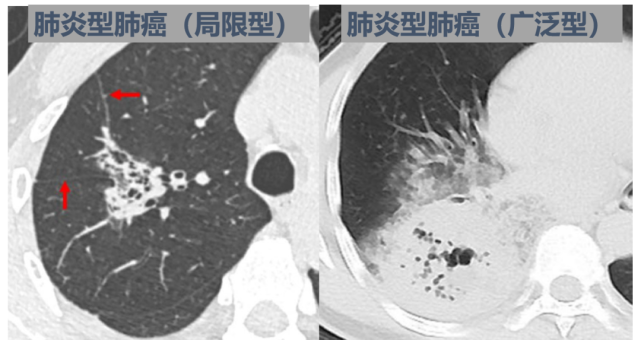

进一步的分析中,作者将这部分患者划分为两类

一类是,局限性肺炎,即肺炎累及范围不及肺叶的50%;

一类是,广泛性肺炎,即肺炎累及范围超过肺叶的50%。

最终,发现两种肺炎的病理类型非常具有代表性。

76.7%的局限型肺炎患者,是腺泡为主型肺腺癌;

80.8%的广泛型肺炎患者,是粘液腺癌。